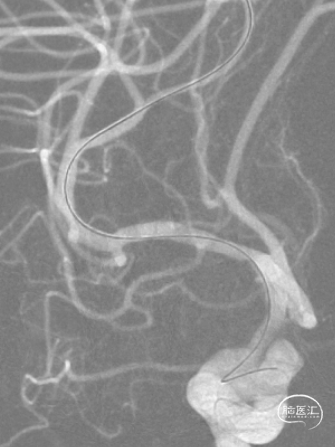

术前影像资料

诊疗经过